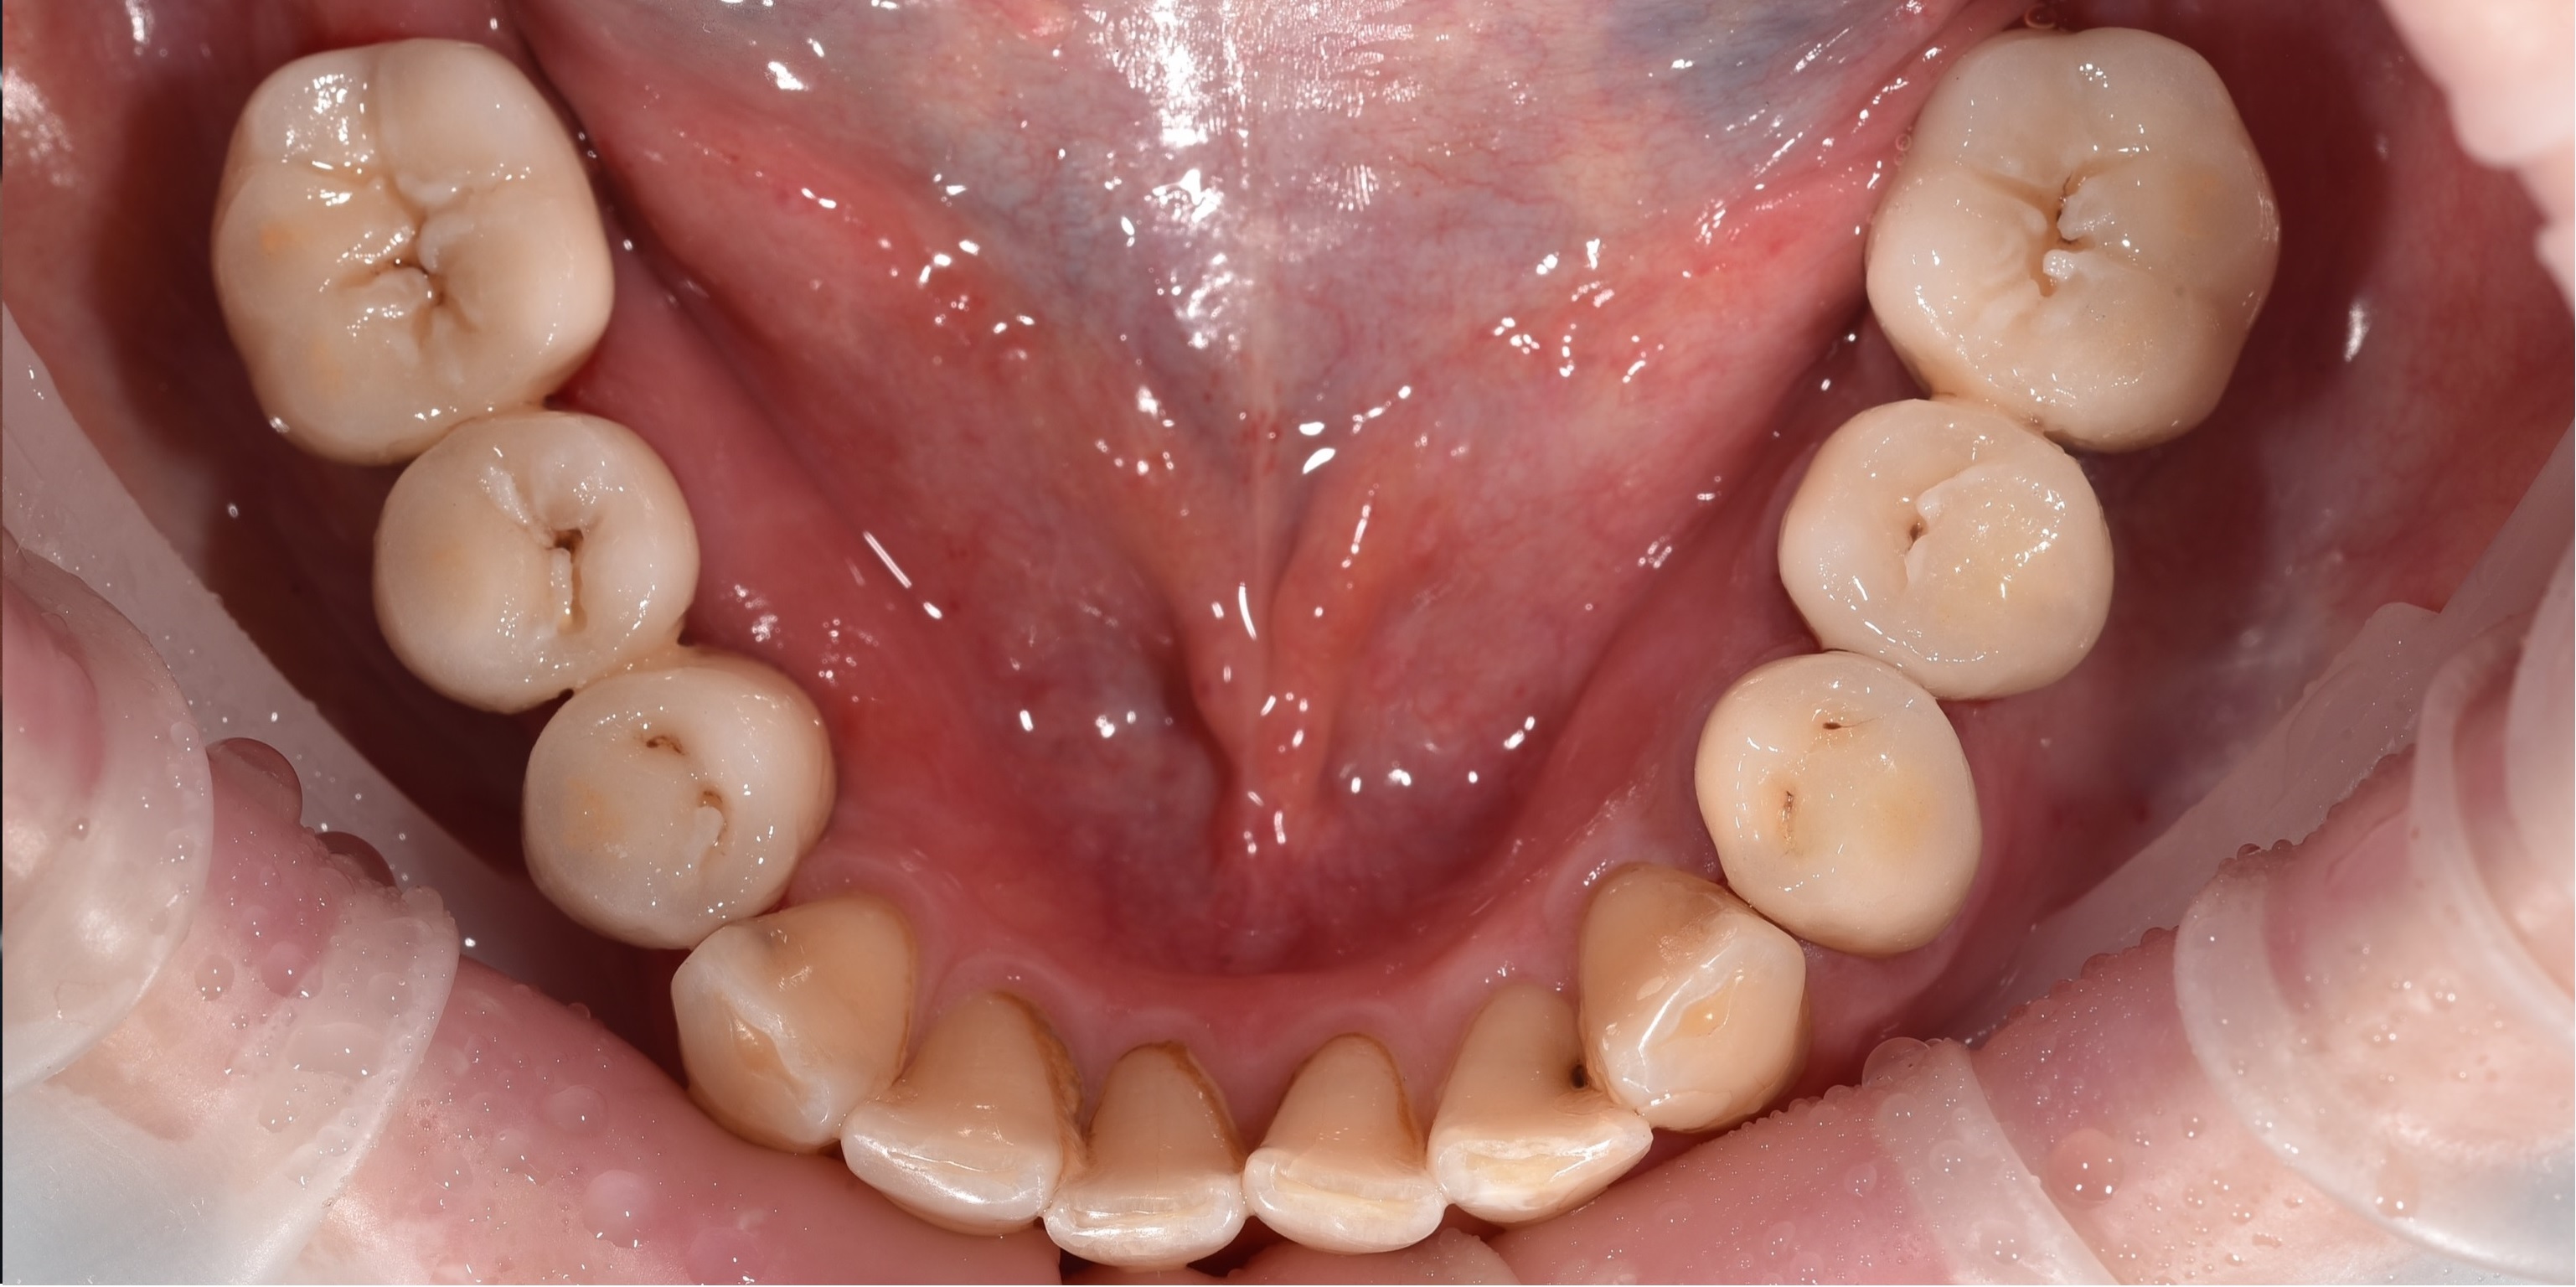

До

После

До

После

До

После

До

После

До

После

До

После